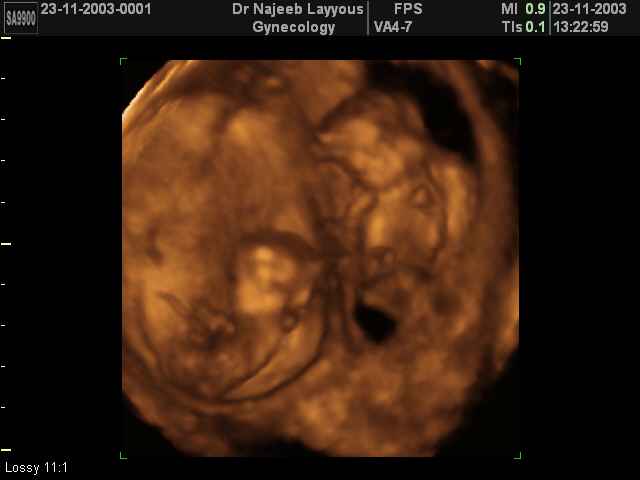

- لقطات فيديو للجنين بجهاز الموجات فوق صوتية رباعي الأبعاد

- صور لوجه الجنين في داخل الرحم

- صور لتصرفات الجنين داخل الرحم

- صور لتوائم

صور لتوائم بجهاز الالتراساوند ثلاثي الأبعاد | الدكتور نجيب ليوس